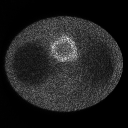

Refer to caption Refer to caption Refer to caption

Figure 5: Reconstructed images of experiment 2. The images reconstructed by the TV-, hard- and soft-superiorized EM algorithms 1 and 2 are displayed in columns 2, 3 and 4, and rows 1 and 2, respectively.

Table 2: TV, l1superscript𝑙1l^{1}-norm, RMSE and iterations of the images of experiment 2.

EM TV-alg 1 hard-alg 1 soft-alg 1

TV(×103absentsuperscript103\times 10^{3}) 13.739 13.105 13.396 13.061

l1superscript𝑙1l^{1}(×103absentsuperscript103\times 10^{3}) 6.729 6.452 6.451 6.277

RMSE 0.2822 0.2778 0.2802 0.2795

iteration 8 8 8 8

mean TV-alg 2 hard-alg 2 soft-alg 2

TV(×103absentsuperscript103\times 10^{3}) 7.167 9.769 5.733 5.576

l1superscript𝑙1l^{1}(×103absentsuperscript103\times 10^{3}) 4.037 5.069 1.434 1.283

RMSE 0 0.2490 0.2091 0.2064

Iteration 9 12 10

From the observations of figures 5 and 6, and table 2, we can draw the same conclusions as the experiment 1. Comparing figures 3 and 5, we can see that the visual quality of the images reconstructed from data set 2 are inferior to those reconstructed from data set 1 because of the low count level. And the performance of the superiorized EM algorithms 2 are much more remarkable than the superiorized EM algorithms 1 for data set 2.

Comparing the results of the two experiments above, we can observe that the TV-superiorized EM algorithm 2 is better in terms of RMSE, while the l1superscript𝑙1l^{1}-superiorized EM algorithms 2 in terms of TV and l1superscript𝑙1l^{1}-norm values. In addition, the thresholding operations cause the Gibbs oscillations in the reconstructed images by l1superscript𝑙1l^{1}-superiorized EM algorithms 2.